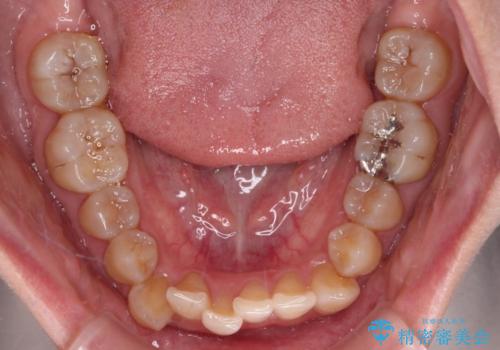

【モニター】下顎前歯のデコボコをインビザラインできれいに

- 下顎の八重歯を気にして来院された患者様です。

下顎前歯にデコボコが集中していたため、顎間ゴムによる後方移動とIPR(歯と歯の間を削ること)により歯列を整えることとしました。

下顎前歯のデコボコが集中しており、奥歯の咬み合わせは、上顎に対して下顎が前方位にある状態でした。下顎の歯列を後方へ移動させる治療はインビザラインの得意とするところですので、1年程度で無事に治療を終えることができました。